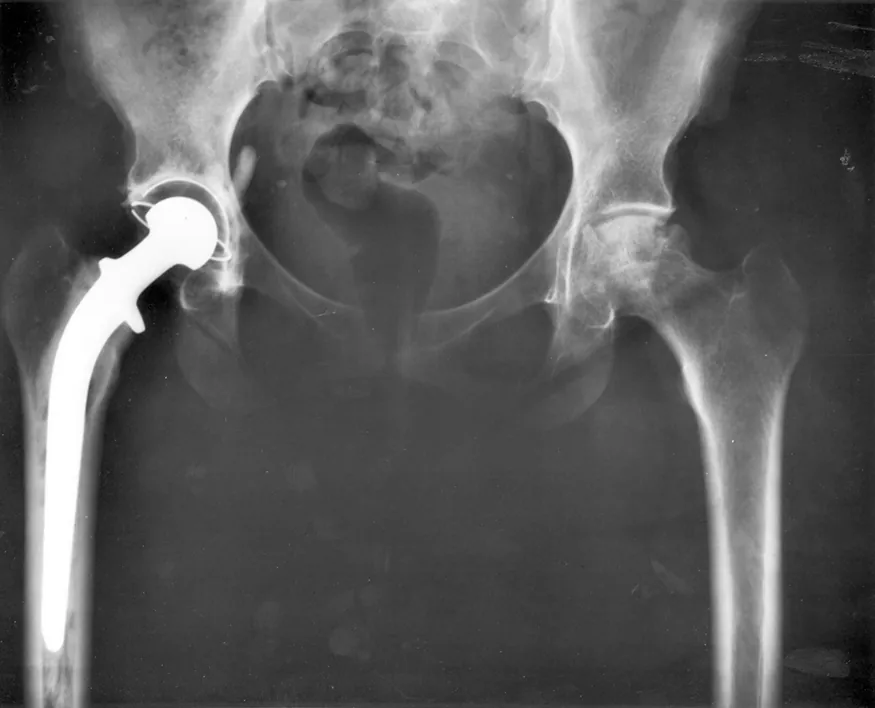

An x-ray image of a person's hips. The right hip joint (on the left in the photograph) has been replaced. A metal prosthesis is cemented in the top of the right femur and the head of the femur has been replaced by the rounded head of the prosthesis. A white plastic cup is cemented into the acetabulum to complete the two surfaces of the artificial ball and socket joint.

Figure 5.1 Total hip replacement surgery has become a common procedure. The head (or ball) of the patient's femur fits into a cup that has a hard plastic-like inner lining. (credit: National Institutes of Health, via Wikimedia Commons)